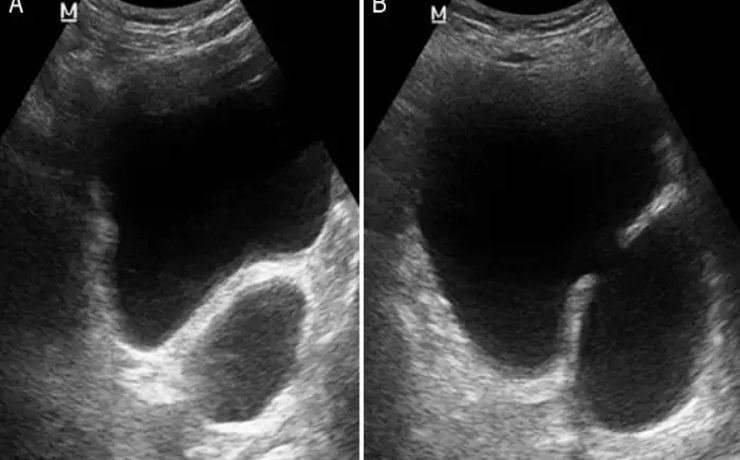

El objetivo del presente artículo es demostrar que la medición ecográfica del cordón umbilical es un factor que puede predecir la macrosomia fetal. Para lo cual se llevo a cabo un estudio descriptivo, observacional en mujeres gestantes a término cuyos factores de inclusión fueron gesta de 37 semanas, producto único